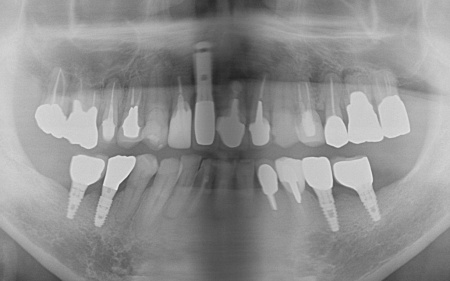

70代男性 右下奥歯を抜いてインプラント治療で噛み合わせを回復した症例

拝見したところ、右下奥歯(第2小臼歯)の周辺組織に炎症が広がり、歯茎が赤く腫れていました。

顎の骨に人工歯根を埋入し、その上から人工歯を装着する方法です。

まず、右下奥歯(第2小臼歯)を抜き、骨が治癒するのを待ってから、インプラントを埋入します。

インプラントと顎の骨がしっかりと結合したら、精密な型取りを行い、インプラント上部に装着する最終的な被せ物を作製しました。

最後に完成した被せ物を装着し、見た目や噛み合わせに問題がないことを確認して、治療を終了しています。